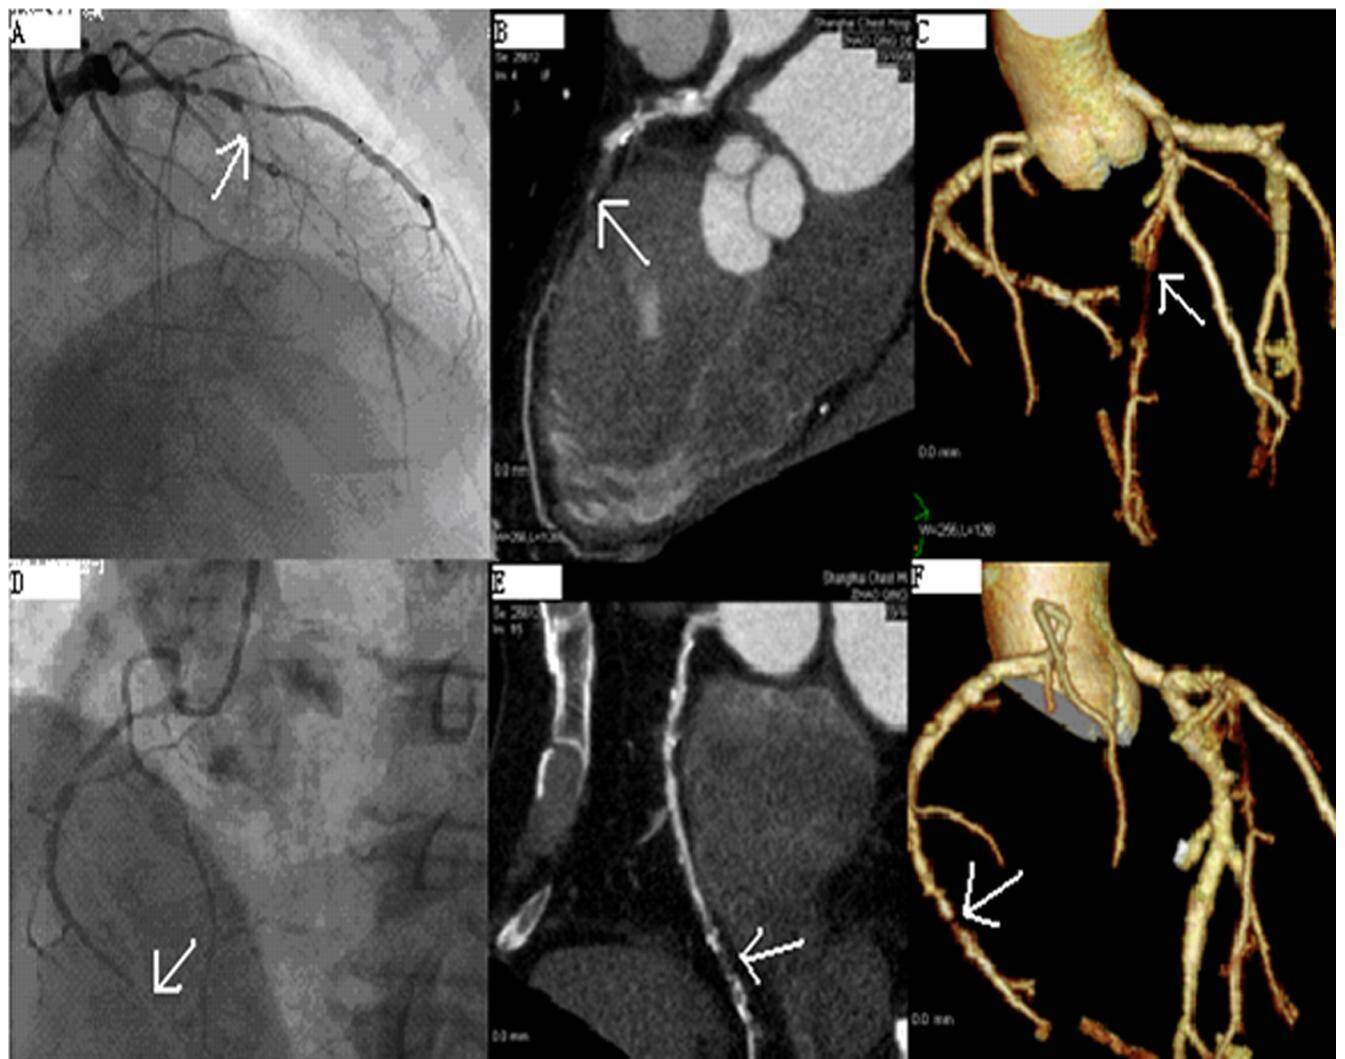

而要想真正搞清楚冠状动脉内是否长有斑块,临床上最常用的检查技术有两种,一种是“冠脉CTA”,另一种则是“冠脉造影”。

不过,由于这两种检查的成本都较高且需要受检者承受X线辐射与碘对比剂的相关风险,所以,它们都并没有被作为常规的体检项目来使用。

一般情况下,也都是在医生高度怀疑可能存在冠心病时,才会建议使用这两种检查技术来仔细观察冠状动脉内的情况。